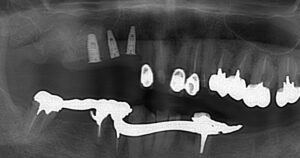

このように奥歯にしっかりとインプラントが

入りました。

歯が増えています。

その後インプラントを埋入しました。